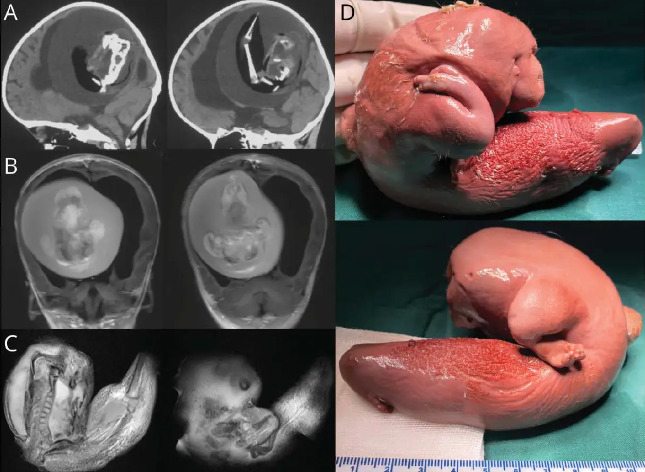

▶ 임부의 알코올 중독 현상 → 태아 알코올 증후군

- 중앙 신경계통 미성숙으로 인한 낮은 지능

- 출생 시 몸무게와 키가 평균치보다 낮음

- 턱 모양이 정상인과는 다름